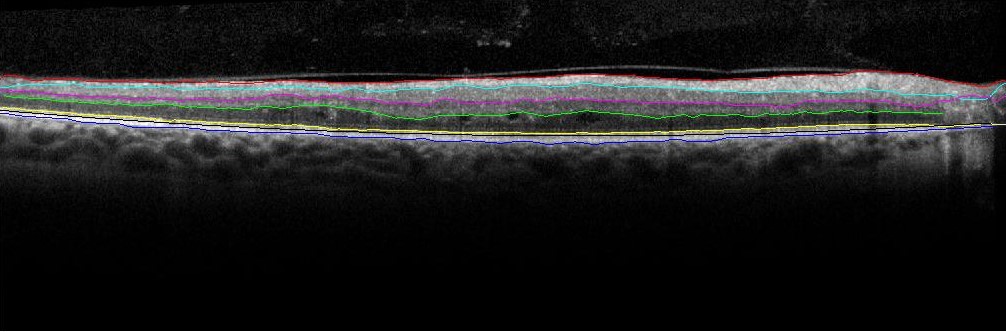

The two key steps for automated denoising and segmentation of the sub-retinal layers from OCT images are described in the following subsections. From all the OCT data image stacks each OCT image is treated as a separate standalone image while denoising and segmenting the sub-retinal surfaces. This operation of separately segmenting each image without any information regarding the adjacent images from the OCT image stack is different from the existing graph-based segmentation approaches in [16]. Once each image is denoised, 7 sub-retinal surfaces, i.e., Surface 1 to Surface 7, and 6 sub-retinal layers that are then segmented are shown in Fig. 1. The segmented sub-retinal layers extend from the inner limiting membrane (ILM, Surface 1) to the Bruch’s Membrane (BM, Surface 7) surface. The automatically segmented sub-retinal layers as shown in Fig. 1 are: the Nerve Fiber Layer (NFL, between Surface 1 and Surface 2), Inner Plexiform Layer (IPL) and Ganglion Cell Layer (GCL) combined (IPL/GCL, between Surface 2 and Surface 3), Inner Nuclear Layer and outer plexiform layer combined (INL, between Surface 3 and Surface 4), Outer Nuclear Layer (ONL, between Surface 4 and Surface 5), Photoreceptor Inner/Outer Segment (IS/OS, between Surface 5 and Surface 6) and Retinal Pigment Epithelium (RPE, between Surface 6 and Surface 7). Additionally, to analyze the average retinal thickness two more combined layers are analyzed as: the Inner layer, that combines the NFL, IPL/GCL, INL and ONL (between Surface 1 and Surface 5), and the Outer layer, that combines the IS/OS and RPE layers (between Surface 5 and Surface 7).

Refer to caption

Figure 1: The manually segmented Sub-retinal surfaces and layers in OCT images. The 7 sub-retinal surfaces are color coded as Surface 1 (Red), Surface 2 (Cyan), Surface 3 (Pink), Surface 4 (Green), Surface 5 (Yellow), Surface 6 (Black), Surface 7 (Blue). The sub-retinal layers are: NFL, IPL/GCL, INL, ONL, IS/OS, Inner and Outer layers.